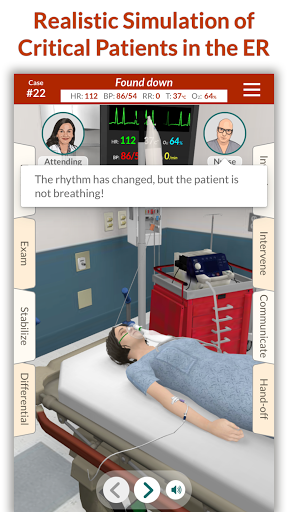

Đào tạo mô phỏng theo yêu cầu của Full Code với các bệnh nhân ảo thực tế cho phép bạn thực hành các trường hợp phức tạp và nâng cao kỹ năng của mình bất cứ khi nào bạn có thời gian nghỉ ngơi, bất kể bạn ở đâu, trên các thiết bị bạn đã sở hữu. CẢI THIỆN SỰ TỰ TIN

Các trường hợp có thể lặp lại vô hạn của Full Code đo lường các kỹ năng trong cả chẩn đoán và quản lý, cho phép bạn học hỏi từ những sai lầm của mình trong một môi trường không có rủi ro. Xây dựng năng lực để bạn có thể đối mặt với các trường hợp thực tế phức tạp một cách tự tin.

-- Bệnh nhân mất bù & ngừng tim --

Mỗi giây đều có giá trị! Bây giờ những bệnh nhân ốm yếu nhất của chúng tôi có thể tử vong nếu bạn không ổn định họ đủ nhanh.

Bệnh nhân và cảnh của chúng tôi trông và âm thanh chân thực hơn bao giờ hết.